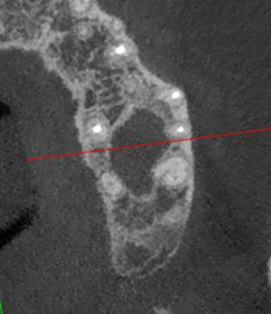

Сохранение зуба при наличии кисты, проростающей в гайморову пазуху

Проблема: У пациента боли в проекции гайморовой пазухи, заложенность носа, боли при пережевывании пищи.

Лечение: Проведено эндодонтическое перелечивание зуба под микроскопом: удалены ранее внесённые материалы, выполнена тщательная механическая и медикаментозная обработка корневых каналов с учётом их анатомии. Особое внимание уделено устранению инфекционного очага (кисты), связанного с воспалением в области гайморовой пазухи. После этого каналы герметично запломбированы, а коронковая часть зуба временно восстановлена для дальнейшего покрытия зуба коронкой.

Результат: После проведённого эндодонтического лечения болевые ощущения при жевании устранены, дискомфорт и давление в области гайморовой пазухи исчезли, восстановилось нормальное носовое дыхание. Зуб сохранён, его функция восстановлена. После фиксации коронки полностью восстановлены анатомическая форма и жевательная эффективность, нагрузка распределяется корректно.